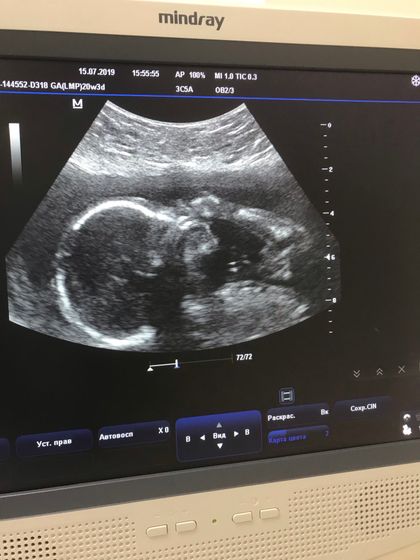

Привет всем ? сделала вчера Узи у Харитоновой. Посмотрела она меня и сказала, что все хорошо, никаких особенностей в развитии плода не видит, что развивается в свой срок, весим уже 320гр, соответсвуем своему сроку ?Чему я очень рада, единственное что меня насторожило, это дополнительная хорда в сердце, но она сказала мне, ничего тут страшного нет, это в норме. В остальном все на своих местах как говорится. Про Рост малышки я не услышала, но наверняка тоже соответствует ?подтвердила девочку ??чему я снова обрадовалась. Малышка пиналась как только могла во время осмотра ❤️. В общем вот такие параметры у нас на 20-21 неделю беременности…